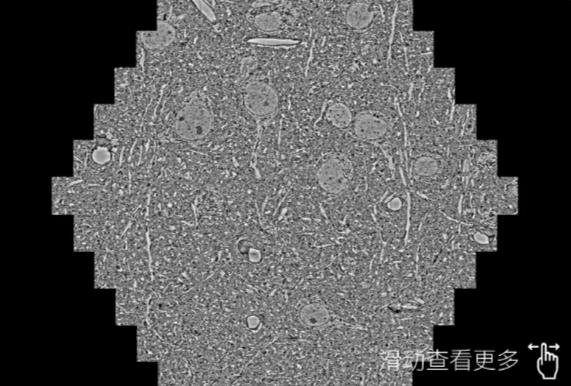

鼠脑切片。左图使用贺州蔡司贺州扫描电镜MultiSEM706对165μmx143pm面积区域成像,耗时仅需1.5秒。右图为鼠脑切片中30μm区域放大效果。样品由芝加哥大学B.Kasthuri提供。

使用蔡司高速贺州扫描电镜MultiSEM对1mm²人脑皮层组织进行高分辨成像,并对其中的各种细胞结构进行三维重构分析。左图展示了2x3mm²组织平面中锥体神经元的三维重构效果。右图显示了局部体积神经元三维重构。图像由哈佛大学chtman实验室提供,渲染图由D. Berger 制作。